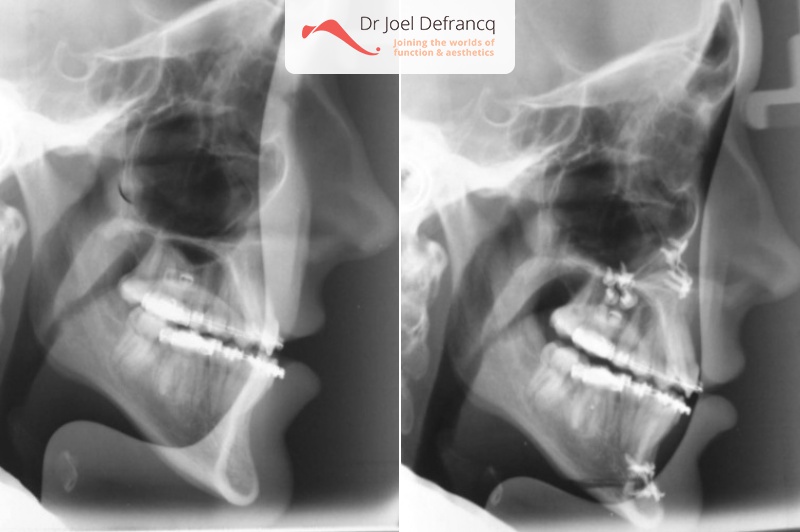

Diagnose van het gezicht

- Te kleine bovenkaak

- Te smalle bovenkaak

Kaakchirurgie

- Verlenging bovenkaak (Le Fort I)

- Kinchirurgie

- Verbreden bovenkaak (Smile distractor)